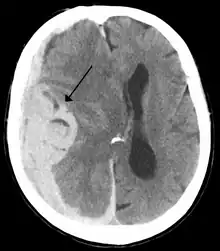

Midline shift is a shift of the brain past its center line.[1] The sign may be evident on neuroimaging such as CT scanning.[1] The sign is considered ominous because it is commonly associated with a distortion of the brain stem that can cause serious dysfunction evidenced by abnormal posturing and failure of the pupils to constrict in response to light.[1] Midline shift is often associated with high intracranial pressure (ICP), which can be deadly.[1] In fact, midline shift is a measure of ICP; presence of the former is an indication of the latter.[2] Presence of midline shift is an indication for neurosurgeons to take measures to monitor and control ICP.[1] Immediate surgery may be indicated when there is a midline shift of over 5 mm.[3][4] The sign can be caused by conditions including traumatic brain injury,[1] stroke, hematoma, or birth deformity that leads to a raised intracranial pressure.

Doctors detect midline shift using a variety of methods. The most prominent measurement is done by a computed tomography (CT) scan and the CT Gold Standard is the standardized operating procedure for detecting MLS.[5] Since the midline shift is often easily visible with a CT scan, the high precision of Magnetic Resonance Imaging (MRI) is not necessary, but can be used with equally adequate results.[5] Newer methods such as bedside sonography can be used with neurocritical patients who cannot undergo some scans due to their dependence on ventilators or other care apparatuses.[6] Sonography has proven satisfactory in the measurement of MLS, but is not expected to replace CT or MRI.[6] Automated measurement algorithms are used for exact recognition and precision in measurements from an initial CT scan.[7] A major benefit to using the automated recognition tools includes being able to measure even the most deformed brains because the method doesn’t depend on normal brain symmetry.[7] Also, it lessens the chance of human error by detecting MLS from an entire image set compared to selecting the single most important slice, which allows the computer to do the work that was once manually done.[7]